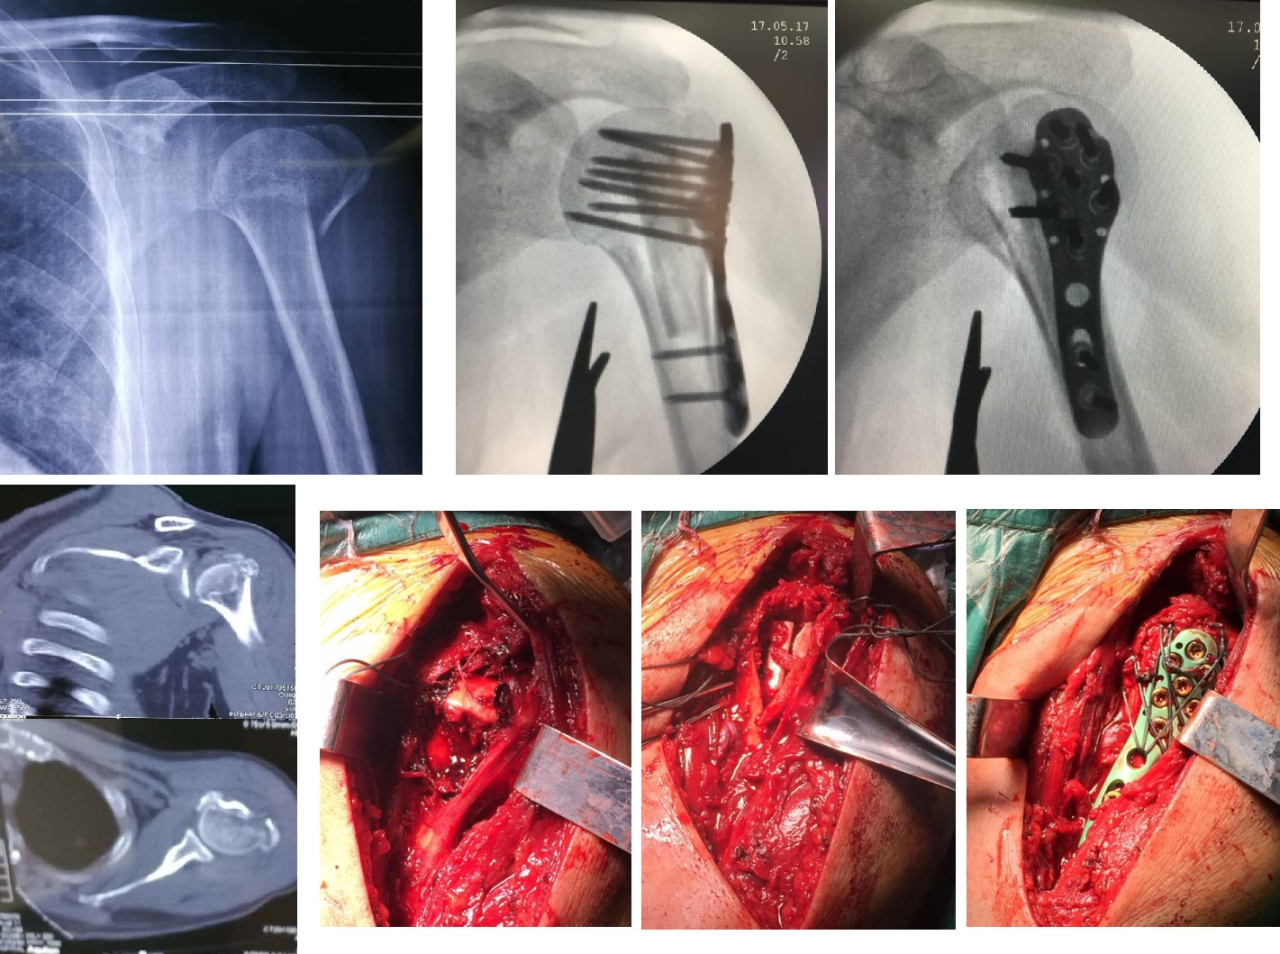

Figure 1 Femme de 65 ans avec une fracture en 4 parties de l'insertion proximale de l'adducteur huméral et une fixation par plaque d'implant fibulaire allogreffe avec incision et repositionnement.